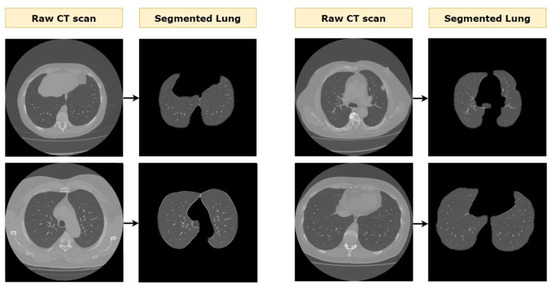

Examples of lung segmentation on various CT scans are presented in Figure 18.

Figure 18. Example outcomes of the lung segmentation process.